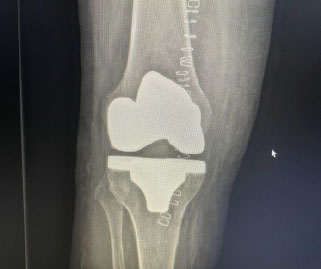

Ejemplo propio Prótesis Total de Rodilla

Genu Varo, Kellgren III-IV

Resultado Prótesis Total Rodilla